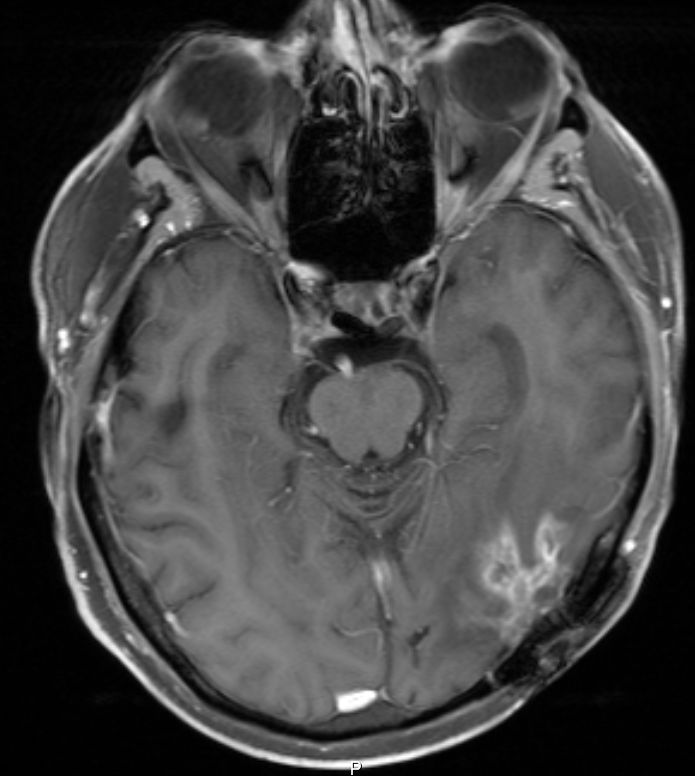

• 54-jähriger Mann, der vor 4 Jahren ein Adenokarzinom des rechten Lungenoberlappens cT4 cN1 M0 entwickelte

•  Cisplatin / Alimta - Chemotherapie, dann Radio –Chemotherapie 50Gy, 3 Zyklen simultan Cisplatin und Pemetrexed

• extrapleurale Oberlappenresektion,  Lymphadenektomie

• postoperatives Stadium ypT3 ypN0 L0 V0 G3

• adjuvante Bestrahlung der Thoraxwand rechts ED 3 Gy, GD 30 Gy

• vor 2 Jahren Metastase links parieto – occipital,  neurochirurgische Entfernung, Bestrahlung des Neurokraniums mit 30 Gy, ED 3 Gy

• vor 1 Jahr  Exstirpation einer Hirnmetaste links occipital, Bestrahlung des Hirnmetastasenbettes links occipital mit 40 Gy, ED 2 Gy

Die linke Spalte zeigt MRTs vor 7 Monaten, die rechte Spalte aktuelle MRTs.

Die MRTs zeigen eine Zunahme der Gadolinium-anreichernden Bezirke. Die Exzision erbrachte Großhirngewebe mit Anteilen einer Nekrose. Kein Tumorgewebe.